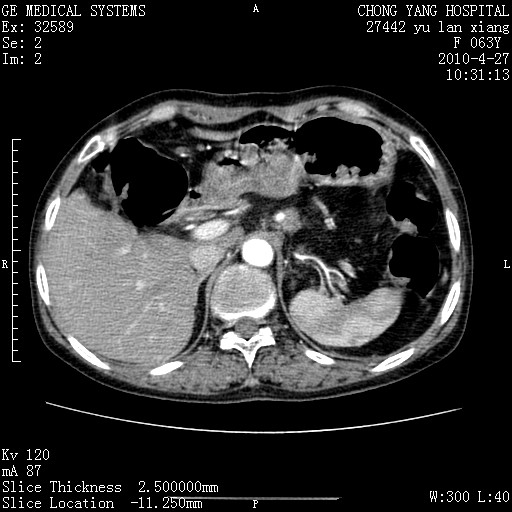

标题: CT26066:F63Y 上腹正中压痛半月,CA199:7400u/ml,MR示胰腺炎伴 [打印本页]

胰腺癌侵犯腹腔动脉干-分支、胃壁、左侧膈肌伴胰周及腹膜后淋巴结转移、胆囊切除术后。

胰腺癌侵犯腹腔动脉干-分支、胃壁、左侧膈肌伴胰周及腹膜后淋巴结转移、胆囊未显影。